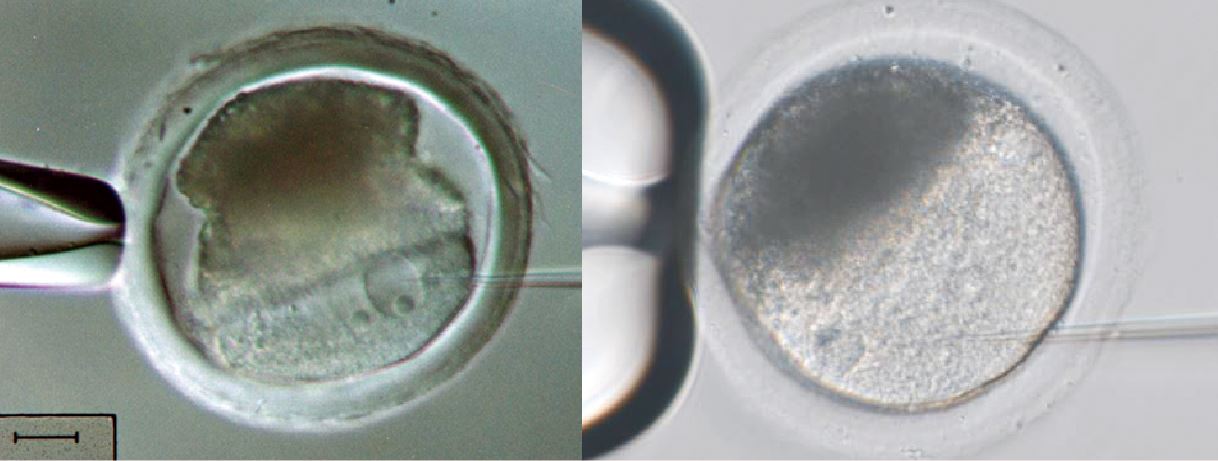

單一精子細胞質顯微注射icsi neolife medical

提高授精率 高倍顯微鏡先篩選精蟲 華人健康網

信不信由你 醫生比你更關注二代試管的成功率 zi 字媒體

你都不知道醫生為提高第二代試管嬰兒的成功率有多努力 每日頭條